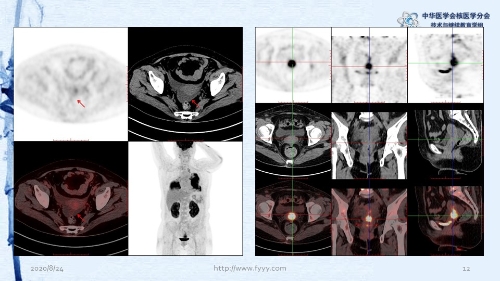

病例82:肉芽肿性血管炎PET-CT显像一例-【CSNM继教学组】郑山 福建医科大学附属第一医院